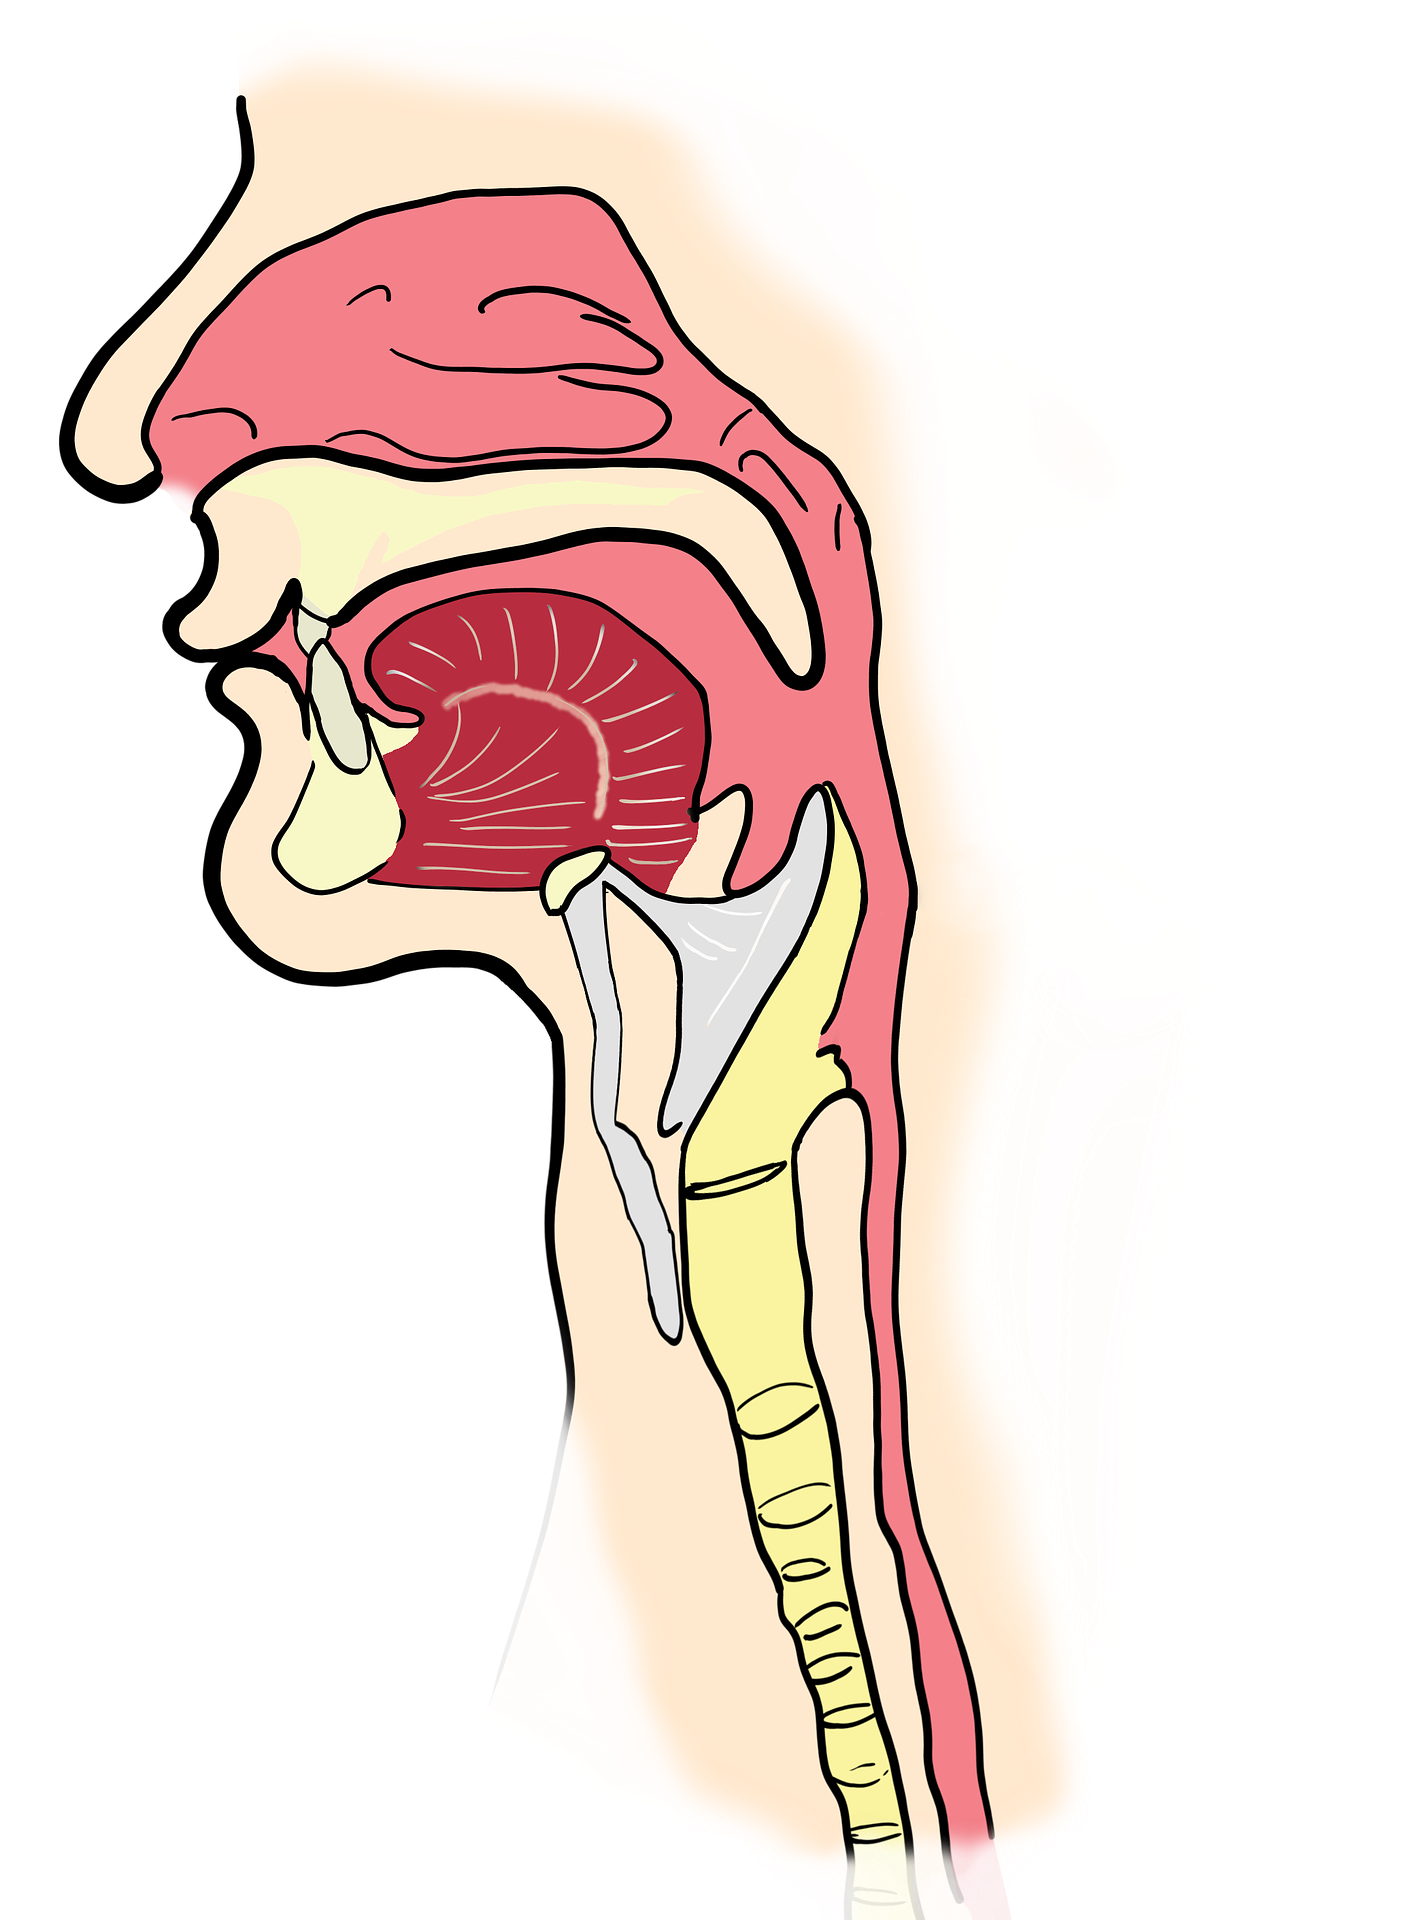

SOLUNUM SİSTEMİ MODELİ

BURUN

Hava giriş ve çıkışı gerçekleşir.

Yapısında kıllar, kılcal kan damarları ve mukus salgısı üreten tabaka bulunur. Burundaki kıllar ve mukus, havayla gelen toz parçalarını tutar.

Mukus havayı nemlendirir. Kılcal kan damarları ise havayı ısıtır.

YUTAK

Ağız ve burun boşluğuyla yemek ve soluk borusunun birleştiği yerdir. Burun yoluyla alınan hava yutağa geçer.

GIRTLAK

Yutak ile soluk borusu arasında yer alır. Yutaktan gelen havayı soluk borusuna iletir. Burada sesin oluşmasını sağlayan ses telleri bulunur.

SOLUK BORUSU

Gırtlaktan gelen havanın akciğerlere ulaşmasını sağlar. Üst üste dizilmiş kıkırdak halkalardan oluşur. İç kısmını kaplayan bir zar vardır.

Bu zar kaygan ve yapışkan bir sıvı üreterek toz ve mikropları tutar. Tutulan toz, mikrop ve yabancı maddeler balgam olarak vücuttan dışarı atılır.

Bronş Ve Bronşcuklar

Soluk borusu akciğere girerken bronş adı verilen iki kola ayrılır.

Bronşlar akciğere girdikten sonra çok sayıda kollara ayrılır. Bu kolların her birine bronşçuk adı verilir. Bronşçukların ucunda alveol adı verilen hava keseleri bulunur.